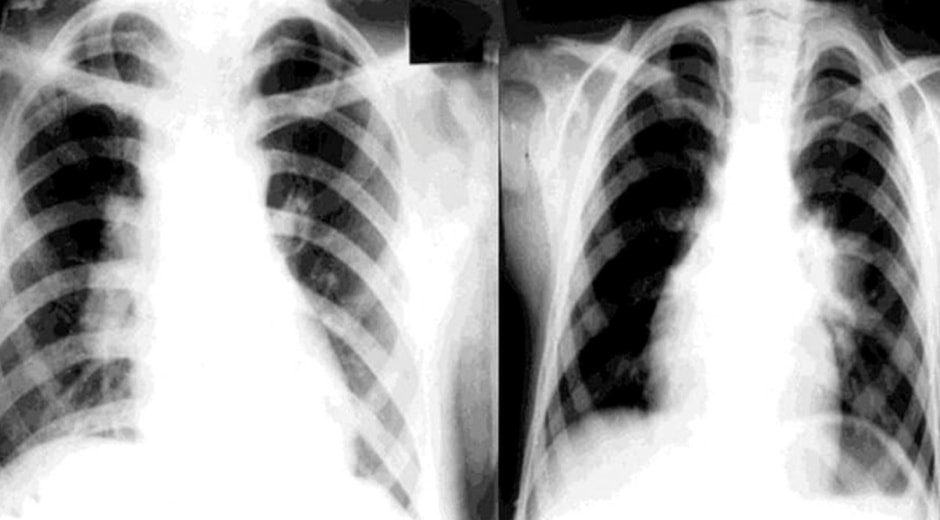

Уже с середины 2026 года в столичных медучреждениях стартует проект по применению нейросетей при проведении цифровой рентгенографии органов грудной клетки. Искусственный интеллект станет надежным ассистентом врачей: он поможет не пропустить минимальные патологические изменения и обработать огромные массивы данных при массовых профилактических осмотрах.

В дальнейшем планируется использовать ИИ для повышения точности диагностики во всех регионах страны.